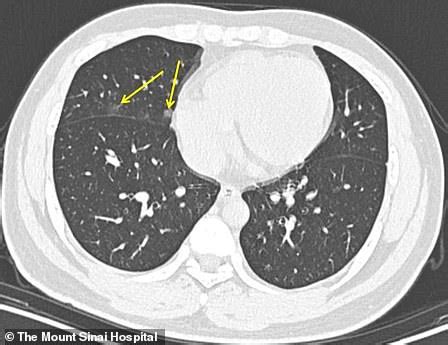

CT scans have become the "first line of defense" in diagnosing suspected infections, especially given the current shortage of testing.

Coronavirus: What X-rays and CT scans reveal about how ...

CT findings for coronavirus may overlap with adenovirus